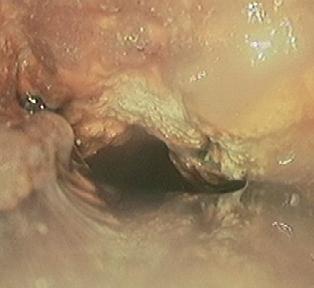

HPV-viruset (humant papillomvirus) kan orsaka cancer i livmoderhalsen. Det är ett vanligt och lurigt virus, du känner inte om du har det. Det kan självläka men i värsta fall kan det leda till cellförändringar som på lång sikt kan utvecklas till cancer –som tar liv.

Det fina är att viruset inte kan undkomma upptäckt. Allt som behövs är en okomplicerad provtagning.

– Jag träffar 15 till 20 kvinnor en till två dagar i veckan som jag tar prov på. Jag informerar dem om viruset, och beslutar vilken uppföljning som behövs utifrån testresultatet, säger Anna Norrsell.

Anna Norrsell har jobbat som barnmorska i drygt 20 år på ungdomsmottagning, barnmorskemottagning, förlossningsavdelning och är nu dysplasibarnmorska på gynmottagningen, vilket innebär att hon tar emot patienter som tidigare haft och blivit behandlade för cellförändringar. – Jag tar även kvinnor som är under utredning. Jag kallar in dem för att kolla om HPV-viruset och om cellförändringarna finns kvar. Är de kvar ser jag till att kvinnorna får uppföljning och träffa en gynekolog, säger hon.

– Många kan tycka ett det är obehagligt och utelämnande att lämna ett cellprov. Jag förstår deras rädsla men vill verkligen att de ska veta att vi tar det försiktigt och att det inte gör ont.

– Jätteviktigt. Hittar vi viruset och cellförändringarna i tid kan vi behandla det. Livmoderhalscancer är den cancerform i världen som tar flest kvinnors liv.

Det finns cirka 200 olika typer av HPVvirus, av dem kan ungefär 15 orsaka cellförändringar på livmodertappen. Virusinfektionen läker oftast ut av sig själv men kan ibland kvarstå och orsaka skada på cellerna. Rökare har större risk att utveckla cellförändringar.

Från det att man smittats tar det ofta flera år innan cellförändringar uppstår. Proverna tas på Gotland och analyseras på Karolinska universitetssjukhusets cytologiska lab.

– Jag tar hand om dem som inte ligger med i screeningprogrammet. Kvinnor med HPV-virusförekomst tas ur screeningen och hamnar hos oss på gynekologiska mottagningen för att vi ska ta en närmare titt på om det finns cellförändringar, säger hon.

Titten kan leda till en utredning som kan leda till behandling som innebär återbesök vart tredje år. Om utredningen visar att det inte finns tecken till cellförändring fortsätter kvinnan att kallas via screeningsystemet.